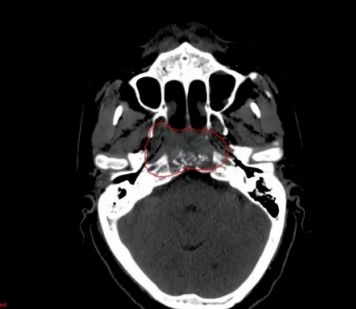

治疗前CT图像

质子治疗剂量分布